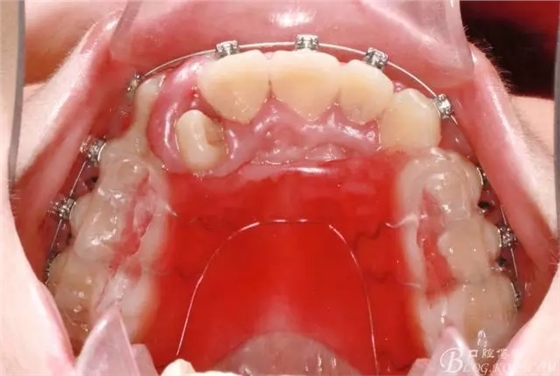

在活動(dòng)頜墊輔助下打開咬合,并對(duì)上頜排齊、擴(kuò)弓;

640.webp (3).jpg

此期間要避免前牙咬合干擾;